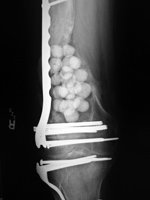

43 year-old man with comminuted right tibia and fibula fractures as well as extensive bone loss and soft tissue injury. A tibial intramedullary nail with proximal and distal locking screws is present as well as multiple rounded bony allografts. There are also large skin staples.